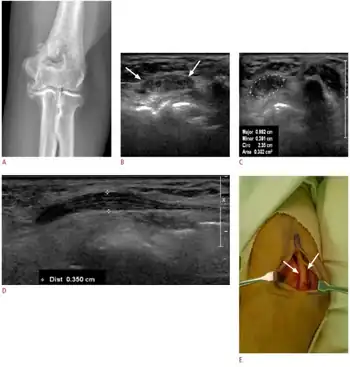

a-d)Images of individual with cubital tunnel syndrome e)operative photograph shows the prominently swollen ulnar nerve